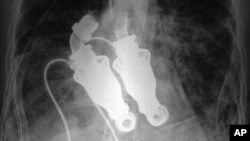

An X-ray shows a continuous-flow artificial heart

These continuous-flow devices have been used for some time to assist the left ventricle of the heart, which is the part that sends blood throughout the body and is the part that most often fails. But the doctors at Texas Heart Institute use a device that is essentially two such pumps put together to replace the functions of both sides of the heart.